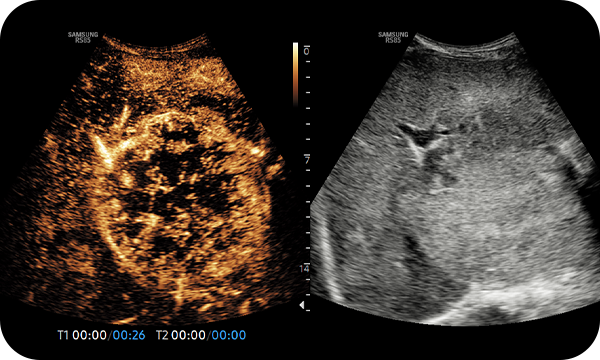

CEUS+ es una tecnología de imagen de mejora de contraste que utiliza las características de los agentes de contraste de ultrasonido. El agente de contraste de microburbujas que se inyecta al cuerpo por la vena o similar se somete a una resonancia no lineal debido a la estimulación de la energía del ultrasonido. Además de la señal no lineal generada por este método, la imagen de contraste de ultrasonido se implementa utilizando la señal armónica y, de esta forma, se utiliza para el diagnóstico basado en las características de contraste a lo largo del tiempo.